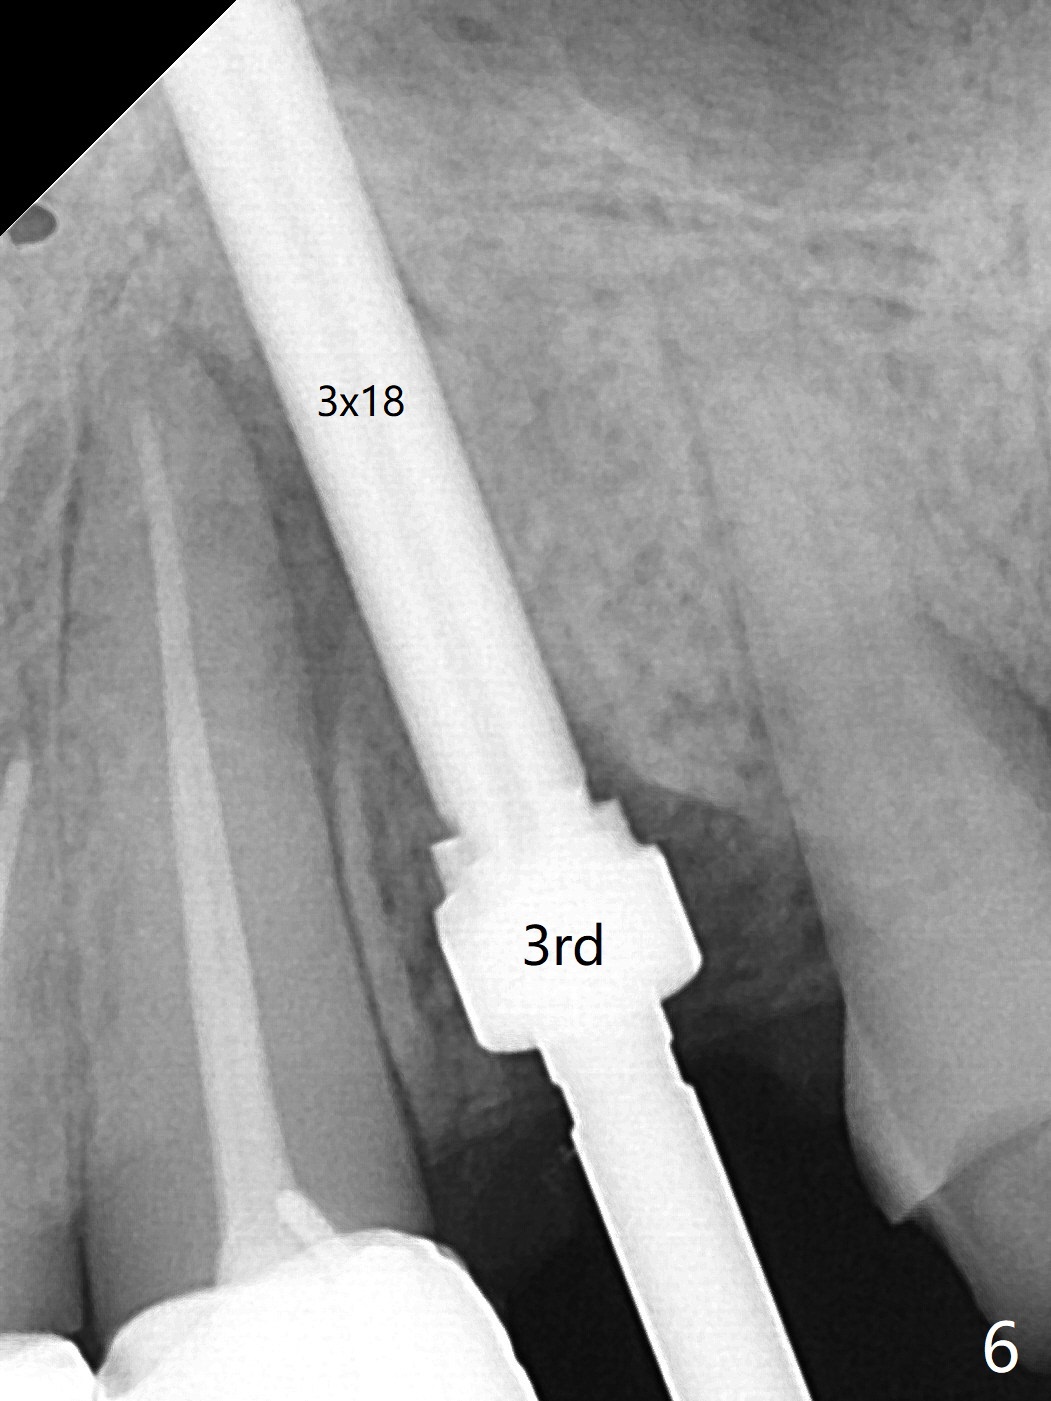

68岁女左上4颊侧瘘道(图一:*),与根尖颊侧骨板缺失相通,其实腭侧根尖周围病变更大(也与颊侧窝相通),术中没有注意腭侧根接近3(图二:P),稀里糊涂的基本顺着腭侧根(颊侧)走向钻洞(图四,与图三理想方向对比),突然记起术前设计钻洞必须在腭侧牙槽窝远中颊侧,在远中建立新洞眼(图五),之后无法再次建立新洞眼,只好利用同一个侧面切割钻头将钻洞往远中移位,同样效果不佳(图六),最后只好放弃,放置粘性骨粉(图七:*),覆盖PRF膜,6个月胶原膜,PGA缝线,牙周胶水。术后重新分析表明顺着腭侧牙槽窝种植与尖牙还是有分离(图八,九:*),因为牙槽窝是斜型的(图十:黑色),不过离颊侧骨板也接近(图八:B)。所以钻洞必须斜型针对远中骨壁,表浅些(图十一:红色箭头);一旦进入骨板,改变角度(图十二:红色箭头),适当矫枉过正,随着植体增大,钻洞会往近中偏移(白色箭头)。最好植体方向理想(图十三)。不过植骨后钻洞偏移可能性比较少。缝线和牙周胶水似乎是一个稳妥固定胶原膜方法。术后病人抱怨水肿严重,术后八天颊侧根尖隆起是由于骨粉推出骨板之外(图十五,十六:*),上颌窦底板无意穿孔(^)伴有上颌窦膜(M)增厚,与术前对比(图十七:上颌窦窦腔清晰)。术后一个月6个月吸收膜不见了,大多数缝线已经脱落,最后两根缝线撤除后,牙槽窝开口已经关闭,好像主要成分是骨粉(图十八)。术后5个月牙槽嵴宽,角化龈也宽,好像可以植入4x11.5毫米植体(图十九)。